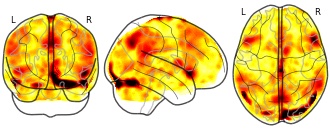

oliver.xie's temporary collection: pmap_L

EmailClick to copy linkLink copied Cite(2023). oliver.xie's temporary collection: pmap_L [Dataset]. http://identifiers.org/neurovault.image:802572niftiAvailable download formatsUnique identifierhttps://identifiers.org/neurovault.image:802572Dataset updatedAug 21, 2023License

Cite(2023). oliver.xie's temporary collection: pmap_L [Dataset]. http://identifiers.org/neurovault.image:802572niftiAvailable download formatsUnique identifierhttps://identifiers.org/neurovault.image:802572Dataset updatedAug 21, 2023LicenseCC0 1.0 Universal Public Domain Dedicationhttps://creativecommons.org/publicdomain/zero/1.0/

License information was derived automaticallyDescriptionCollection description

None

Subject species

homo sapiens

Modality

fMRI-BOLD

Cognitive paradigm (task)

rest eyes open

Map type

Z

zorro's temporary collection: Oliver

EmailClick to copy linkLink copied Cite(2017). zorro's temporary collection: Oliver [Dataset]. http://identifiers.org/neurovault.image:52647niftiAvailable download formatsUnique identifierhttps://identifiers.org/neurovault.image:52647Dataset updatedAug 15, 2017License

Cite(2017). zorro's temporary collection: Oliver [Dataset]. http://identifiers.org/neurovault.image:52647niftiAvailable download formatsUnique identifierhttps://identifiers.org/neurovault.image:52647Dataset updatedAug 15, 2017LicenseCC0 1.0 Universal Public Domain Dedicationhttps://creativecommons.org/publicdomain/zero/1.0/

License information was derived automaticallyDescriptionPositive emotions vs neutral emotions

Collection description

None

Subject species

homo sapiens

Modality

fMRI-BOLD

Cognitive paradigm (task)

Emotion Recognition Task

Map type

T